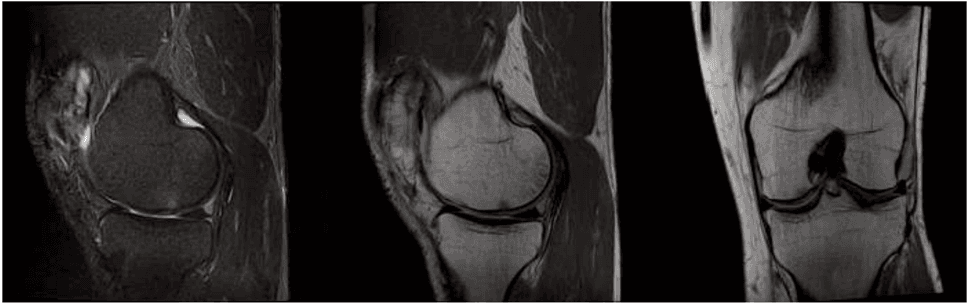

Every case of osteoarthritis is unique and requires meticulous analysis before proceeding with any intervention. At our Milano clinic, the journey begins with an in-depth specialist consultation supported by imaging diagnostics, such as magnetic resonance imaging or high-resolution ultrasound. This phase is crucial for determining the degree of joint wear and the patient's suitability for regenerative medicine.